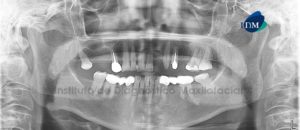

Paciente masculino, 54 años es referido al Instituto de Diagnóstico Maxilofacial para planificación de cirugía guiada con el objetivo de colocar implantes dentales en el